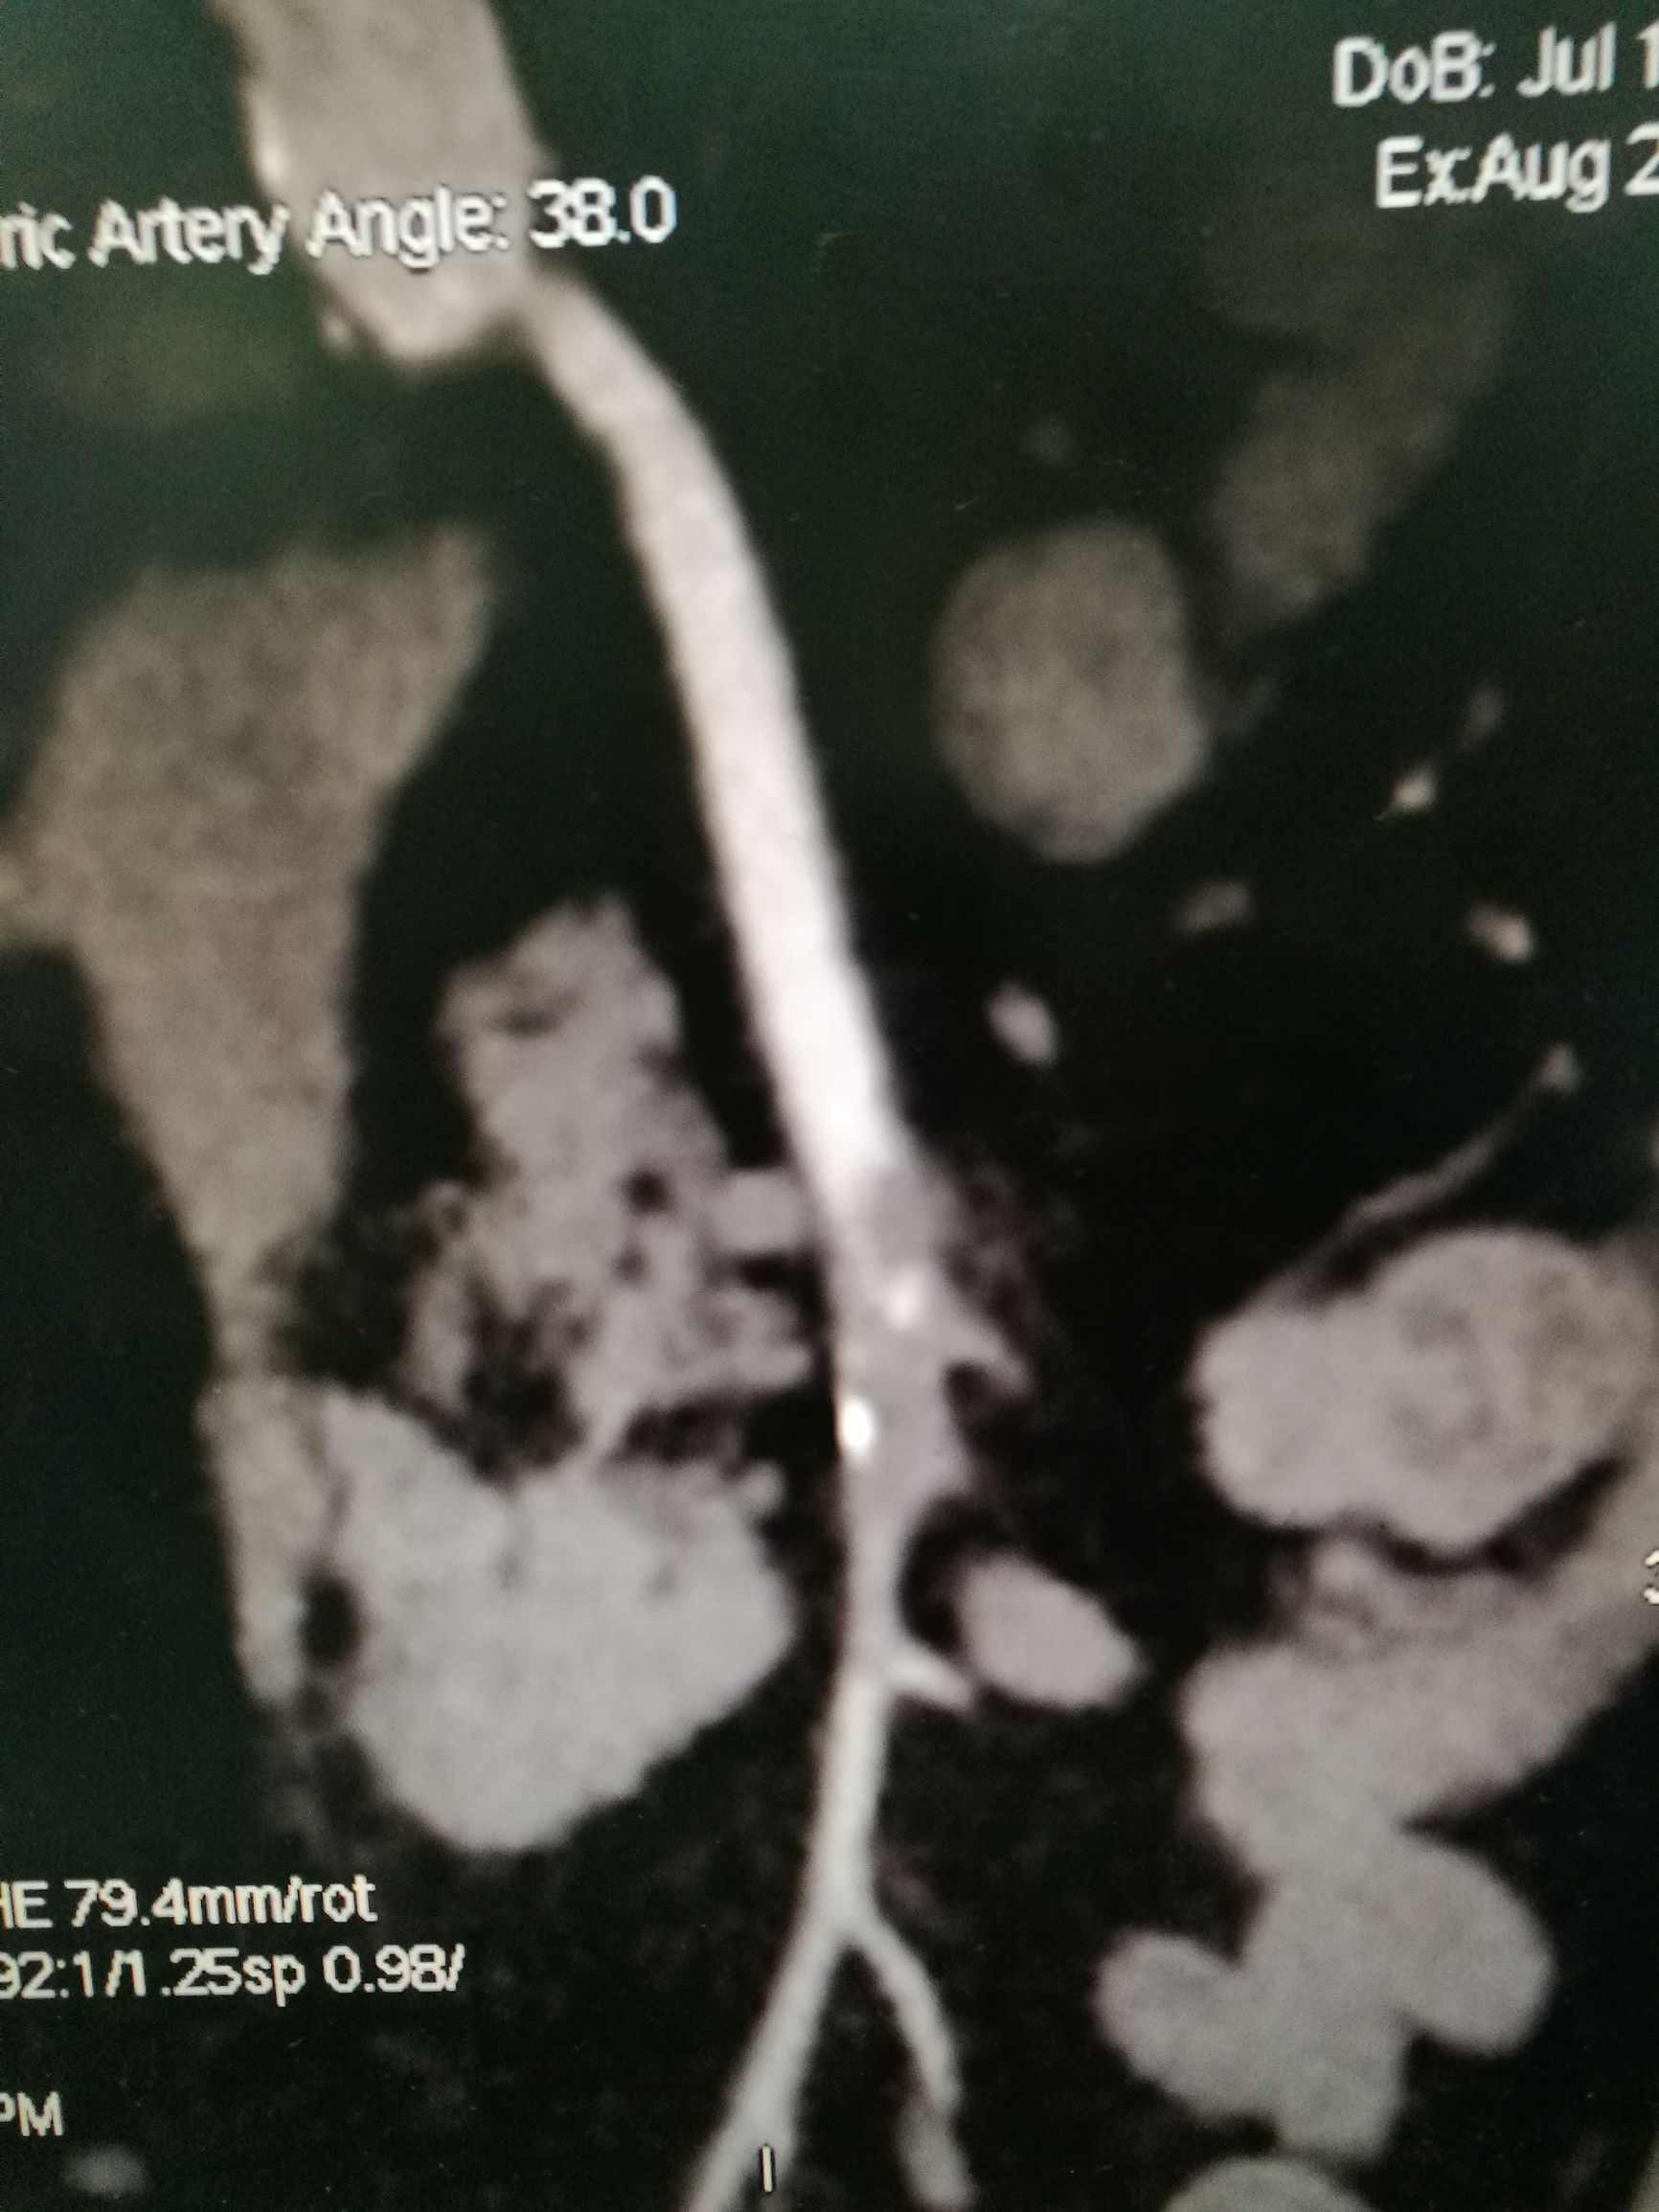

下一台手术室个急性肠缺血的患者。W奶奶近年74岁,突发腹痛14小时来我院看急诊。患者14个小时前突发腹痛,脐周为主,疼痛呈持续性,伴阵发加重,患者既往有冠心病,心脏搭桥病史。来看急诊,急诊医生很警惕,做了个增强CT,可见肠系膜动脉内充盈缺损(图1,2),诊断明确,考虑到患者高龄和心脏病史,决定先尝试微创治疗。

图1. 二维重建片可见肠系膜上动脉内充盈缺损